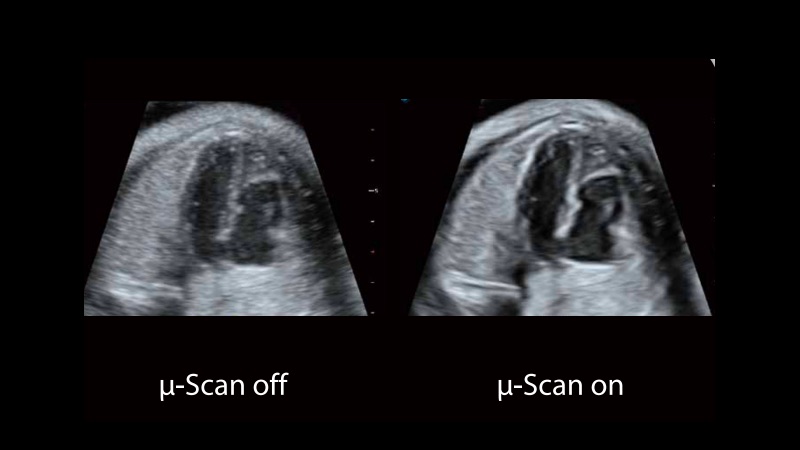

μ-Scan+新一代微米成像技術

新一代微米成像技術大大提高了器官和病變的可見性。高清對比度分辨率將抑制斑點噪聲,同時保持真實的組織結構。